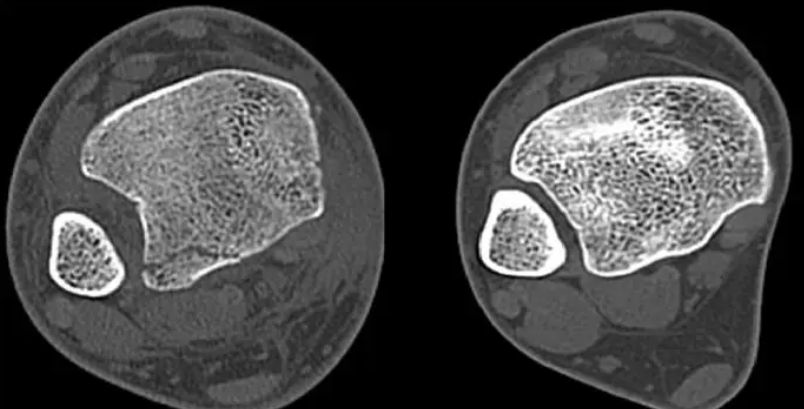

下脛腓聯(lián)合損傷是指脛腓骨下端彼此間的結(jié)構(gòu)損傷,踝穴變寬,距骨向外或向后脫位。

踝關(guān)節(jié)損傷后,在臨床檢查的基礎(chǔ)上,應(yīng)行常規(guī)X線檢查,在前后位X線片上脛骨遠端關(guān)節(jié)面上1cm水平,下脛腓間隙>5mm或脛腓重疊在前后位X線片上<10mm,表明存在下脛腓聯(lián)合損傷。